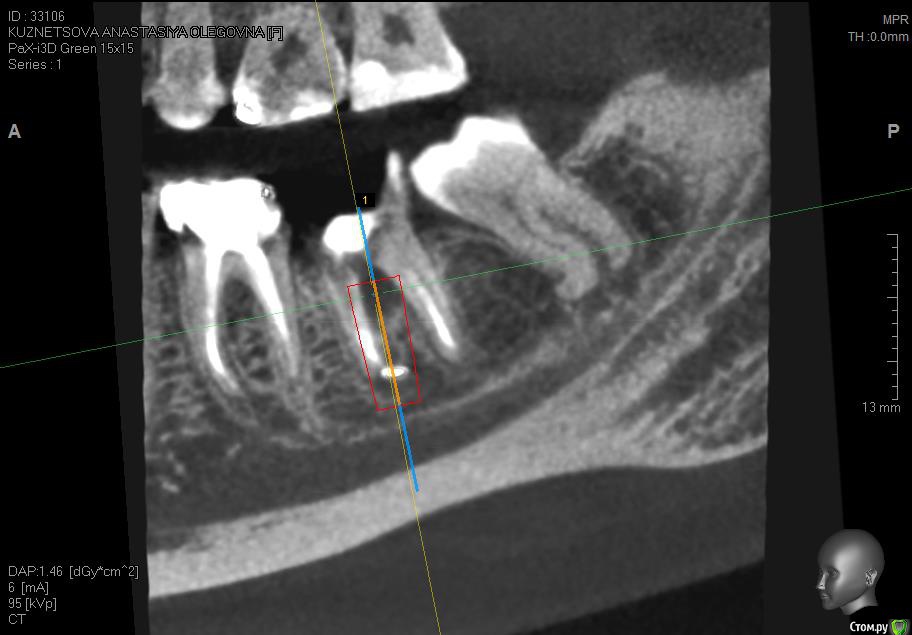

Jurai Опубликовано 8 июля, 2016 Поделиться Опубликовано 8 июля, 2016 Восьмерка как восьмерка, даже не омерзительная. Пока на снимок не посмотришь! Ссылка на комментарий